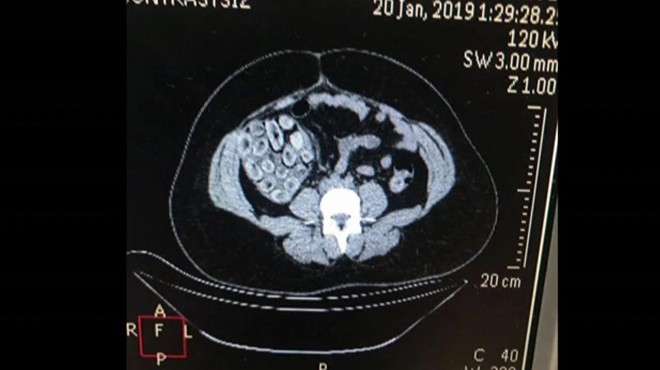

Ekipler yapılan aramada A.D.S.L.'nin uyuşturucu maddeyi kapsül halinde yutmuş olabileceğini değerlendirerek Haseki Eğitim ve Araştırma Hastanesine sevk etti. Hastanede sindirim sistemi röntgen filmi çekilerek kontrol edilen Brezilya uyruklu kadın A.D.S.L.'nin içinde kokain bulunan kapsül şekline soktuğu 115 prezervatifi yuttuğu belirlendi.